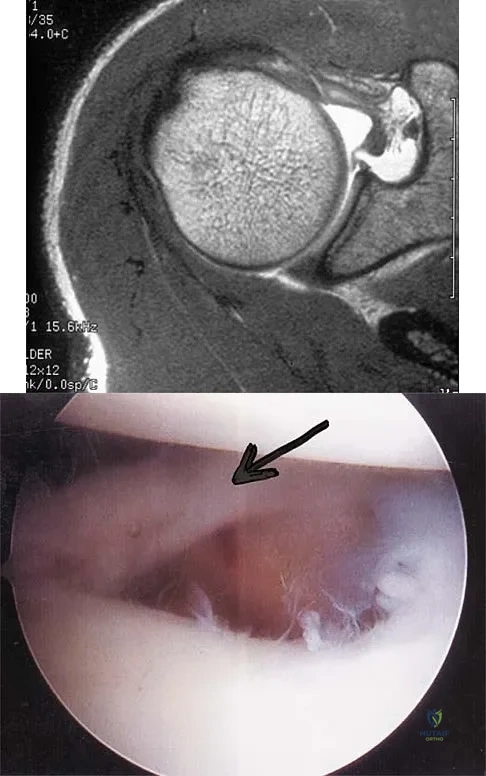

A patient has right shoulder pain. Figure 1a shows a gadolinium-enhanced transverse MRI scan at the level of the coracoid. Figure 1b shows an arthroscopic view of the anterior structures from a posterior portal. These images reveal which of the following findings?

Explanation